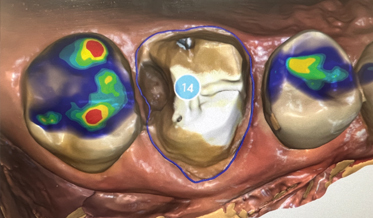

Improving Periodontal Disease Management With Artificial Intelligence